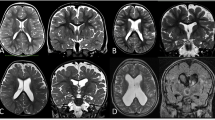

Neuroimaging of the brain is often one of the first steps in the determination of etiology and prognosis of an encephalopathic condition in the newborn. Structural anomalies of the brain are seen with some frequency in this setting. Due to the complex nature of cortical development, both genetic and non-genetic (environmental, toxins, etc.) factors may lead to a very similar pattern on MRI. In recent years, given the advances in genetic sequencing technologies as well as improvements in neuroimaging field, clarity, and technical advances in imaging sick and small infants, progress has been made to identify the genetic underpinnings of many cortical malformations. This has been particularly the case with regard to posterior fossa abnormalities.

Congenital malformations of the posterior fossa are relatively rare but are frequently more recognized, given the continuous improvements of neuroimaging. High-resolution genetic testing has led to identification of the etiology for some, but the cause of many still is elusive. Future application of high-resolution genetic testing such as whole exome sequencing will help identify other variants. MRI patterns may not sufficiently differentiate the clinical entities.